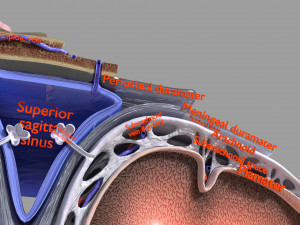

A blend model of brain along with its covering layers (meninges), skull bone and scalp labelled in detail and anatomically precise. The parts depicted are white, gray, pia, arachnoid, dura, bone, skin, fat, aponeurosis, periosteum, falx cerebri and more.